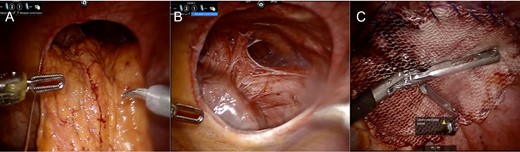

Intraoperative Images from Case #1. (A) Reduction of omentum and transverse colon through hernia defect. (B) Representative image of defect following reduction of intra-abdominal contents; heart border visible to lower left of defect. (C) Following placement of mesh for repair of diaphragmatic hernia.

Intraoperative assessment revealed omentum and transverse colon herniating through the left diaphragm defect (Fig. 2A). This was reduced manually without difficulty. The heart was easily seen through the defect (Fig. 2B). The area of the hiatus was evaluated noting a small hiatal hernia. The paraesophageal hernia was repaired in standard fashion with Nissen fundoplication. Attention was turned to the diaphragm defect which was closed using a running 0 permanent V-lock suture. Subsequently, a 12-cm mesh was underlaid and sewn circumferentially using 0 permanent V-lock suture (Fig. 2C). Intraoperative endoscopy demonstrated ease of passage through the GE junction into the stomach.